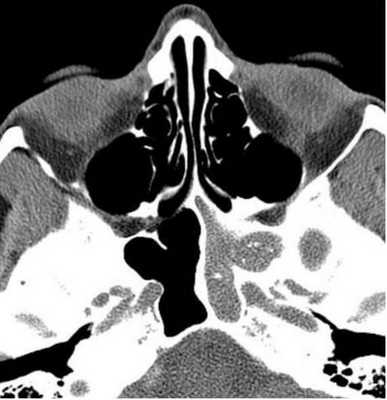

Тотальное заполнение жидкостью (кровью?) левой верхнечелюстной пазухи, повреждение носовой перегородки на компьютерной томограмме

Процедура КТ носа и околоносовых пазух дает возможность изучить строение анатомических структур и выявить особенности патологического процесса. Обследование рассматриваемой области на компьютерном томографе показывает:

деструктивные изменения и травматические повреждения лицевых костей;

утолщение слизистой оболочки носа и синусов;

искривление носовой перегородки;

воспаления внутри пазух (КТ покажет гайморит, фронтит, этмоидит, сфеноидит);

абсцессы носовой перегородки;

полипы, гранулемы, кисты слизистой оболочки воздухоносных полостей лицевого черепа;

опухоли в околоносовых пазухах;

скопление крови, экссудата, гноя в синусах;

инородные тела в носовых ходах и костных углублениях;

кровоизлияния в пазухи и мягкие ткани;

стоматологические патологии (врастание корня или смещение зуба в гайморову пазуху);

воспаления в горле и носоглотке;

остеомиелит лицевых костей;